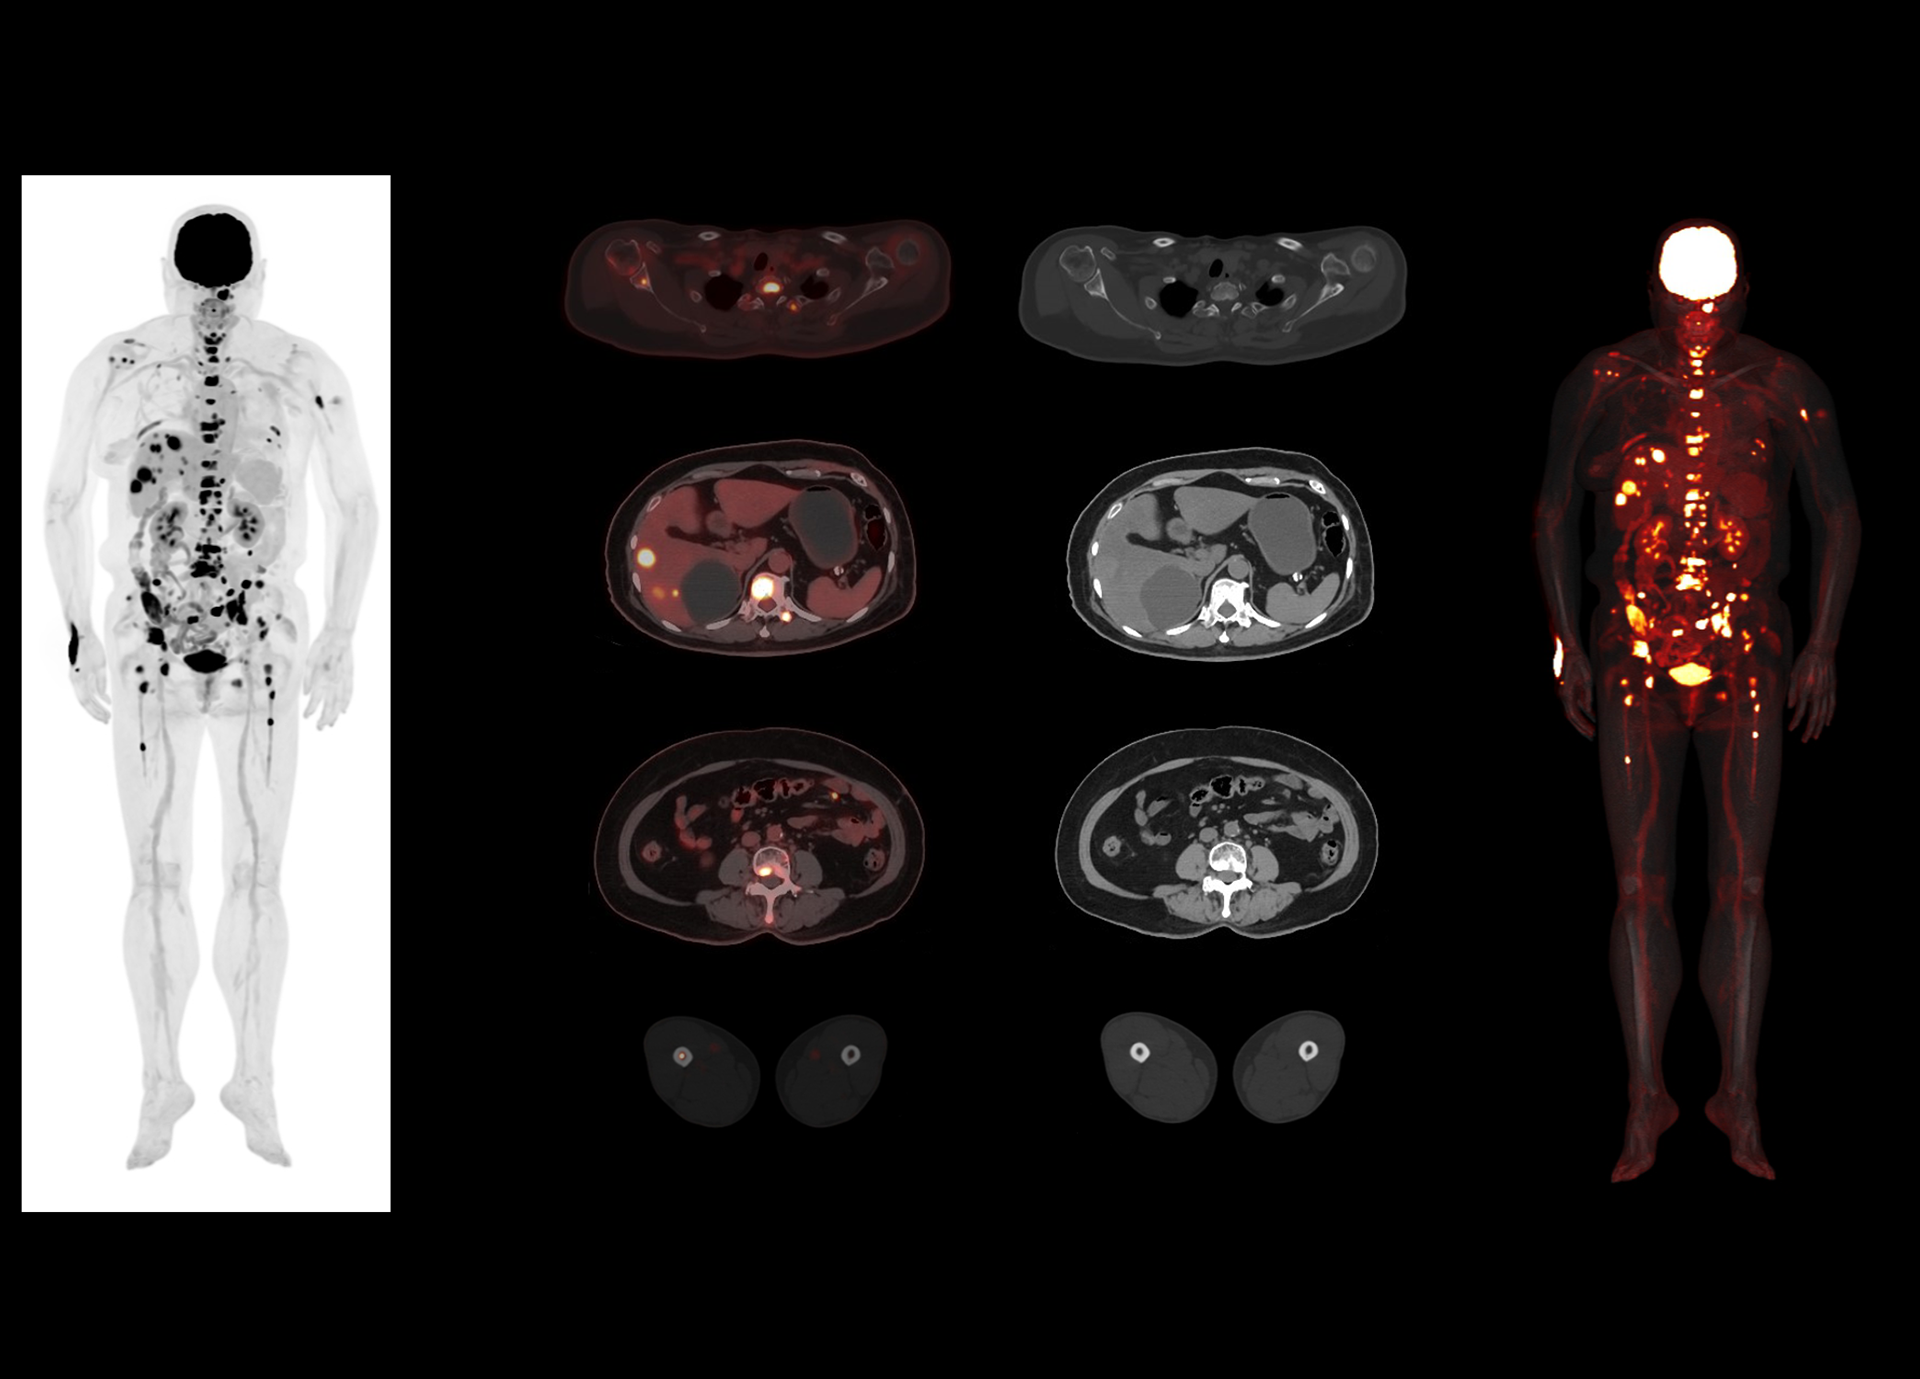

181 cps/kBq and more¹

High effective sensitivity that benefits from TOF gain leverages better diagnostic accuracy under low dose usage and fast scan time.